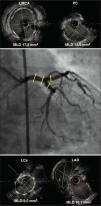

The angiographic and procedural characteristics (Table 2 and Figures 1, 2, and 3) also revealed a complex profile, with over half of patients with LMCA+three-vessel injuries and 82% with involvement of the bifurcation. The distribution of the SYNTAX score was 39.2% for scores between 0 and 22, 42.8% for scores between 23 and 32, and 17.8% for scores≥33. The procedures were performed mostly via femoral artery (86%), in 71% of cases with the use of one stent. 2.8±1.4 stents were used per patient and 93% of patients received drug-eluting stents. The interventions were guided by IVUS and/or FFR in 71.4% of the procedures, and all cases achieved angiographic success.

– Lesion in the left main coronary artery (LMCA)+three vessels, Syntax 28. The right coronary artery was previously treated during an acute coronary syndrome. Lesions of LMCA and left anterior descending artery (LAD) were assessed by intravascular ultrasound and fractional flow reserve, demonstrating a need for revascularization. Sub-occlusive lesion in the proximal third of the left circumflex artery. MLD=minimum lumen diameter.

– Pre-dilation of lesion in left circumflex artery bifurcation and in the proximal third, followed by rotational atherectomy for the left anterior descending artery. Placement of two drug-eluting stents 3.5×32mm for left anterior descending artery and of 3.0×24mm for left circumflex artery with T-stenting technique. Final post-dilation with simultaneous kissing balloons technique.

– Optimization achieved and verified by intravascular ultrasound through the minimal areas of the lumens in the origin of the left anterior descending artery (LAD), let circumflex artery (LCx), the polygon of confluence, and body of the left main coronary artery (LMCA). MLD=minimum lumen diameter; PC=polygon of confluence.